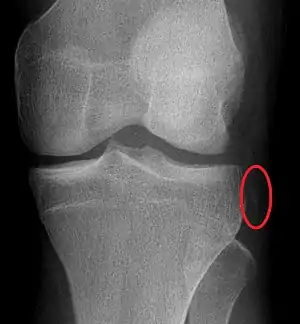

Plain X-rays, CT scan, ultrasonography, or MRI may help with the diagnosis.[2][11] Findings on X-ray that may be useful among those who have already reduced include a variable joint space, subluxation of the joint, or a Segond fracture.[5]

They may be divided into five types: anterior, posterior, lateral, medial, and rotatory.[4] This classification is based on the movement of the tibia with respect to the femur.[11] Anterior dislocations, followed by posterior, are the most common.[2] They may also be classified on the basis of which ligaments are injured.[2]